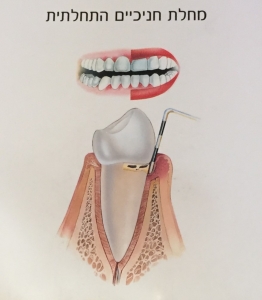

ג'ינג'יביטיס – צורתה הקלה יותר של המחלה, הפוגעת בחניכיים בלבד.

החניכיים הופכות אדומות, נפוחות ומדממות בקלות.

תיתכן תחושת אי-נוחות קלה או כלל לא.

ג'ינג'יביטיס נגרמת לרוב כתוצאה מהיגיינה אוראלית לקויה.

בקבלת טיפול מתאים ובהמשך שמירה על היגיינה תקינה בבית, ניתן להחזיר את המצב לקדמותו ולהגיע להחלמה מלאה.

עם זאת ג'ינג'יביטיס אשר אינה מטופלת עשויה להפוך לפריודונטיטיס עם הזמן.